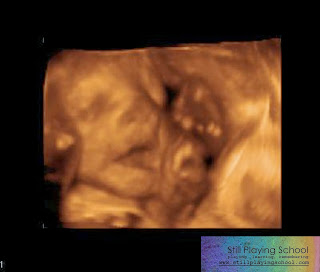

The ultrasound went well! We had Dr. B again who is always reassuring and calm.

Violet has still not stopped growing, which is great. He said that some babies with her diagnosis stop at 20some weeks. But she is measuring small as expected. She is 3 lbs. 11 oz. She has hair that we could see on the back of her sweet, little head. He joked that she might have more than him.

We talked a bit about her individual defects and what each one will mean at birth, but a lot of them (like her enlarged kidneys and possible bowel issues) won't really tell us much by ultrasound. We will have to wait until she is born to see if there is function to them, but he seems to think there is since she is using her kidneys now and there are no obvious places in the bowel that look like they will cause problems.

She isn't breech anymore. She had her face turned away from us so Dr. B used a noise maker that sounded like an air horn to see if she would startle and roll over. He said it doesn't work with most babies but it worked with Violet! She started moving all around! It was so funny! And I am so comforted to know that she can hear (there is a chance she will be deaf and/or at least partially blind) because that means she has been hearing her Momma, Dada, and sister all this time!

When she heard the noise maker she turned around a little so we got some partial shots of her face, but she was still pressed up and cuddled against me "as if her face was smashed into a screen door," Dr. B said. We saw her stick her thumb into her eye and smile! I was so happy to see her personality like this. It made all the ultrasounds and medical bills worth it to see that silly moment and get a picture of it.

We will have one more ultrasound in three weeks. Monday we have a regular OB appointment where we will schedule her c-section date and we will also tour the NICU and meet with Dr. L, Violet's NICU doctor.